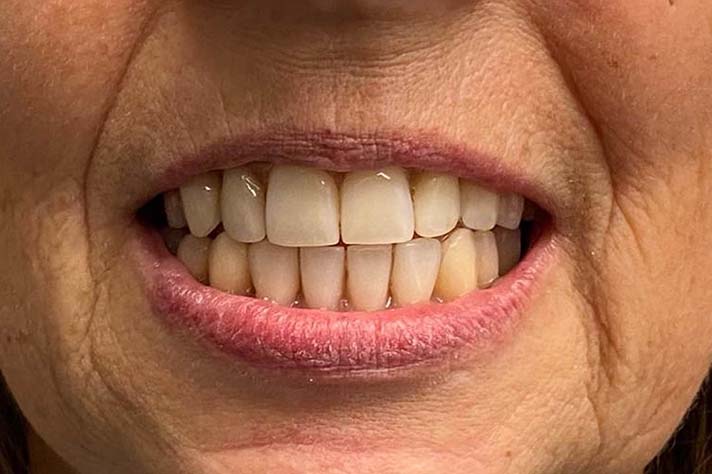

Fazit

Die Alternative zur Behandlung mit festen dritten Zähnen an einem Tag (FDZ) wäre eine herkömmliche Versorgung mit mehreren Implantaten, eine überaus lange Behandlungszeit mit Augmentationen, Einheilungsphasen und einer ausgedehnten Zeit der Zahnlosigkeit. Die Therapie Feste dritte Zähne an einem Tag benötigt dagegen aufgrund der umfangreichen Vorplanung lediglich sechs bis sieben Stunden Behandlungszeit, erhöht die Lebensqualität und verursacht geringere Kosten. Entscheidend für den Erfolg ist die Zusammenarbeit eines Teams aus den Bereichen Chirurgie, Anästhesie, Prothetik und Zahntechnik.